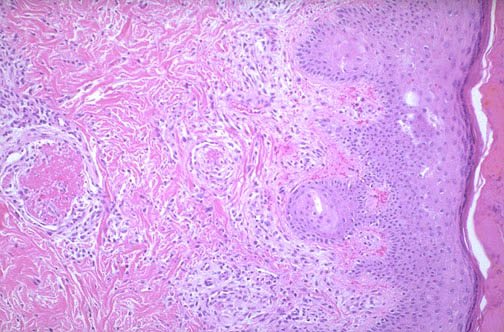

| There is vascular thrombosis in the dermis of the skin in this patient with antiphospholipid syndrome (APS). This syndrome results from presence of autoantibodies directed against anionic phospholipids, such as cardiolipin. This syndrome can occur in patients with SLE, and the antibody interferes with coagulation assays, giving it the name "lupus anticoagulant." However, in vivo, patients have a hypercoagulable state with recurrent arterial and venous thromboses. In preganancy, APS can lead to fetal loss. |